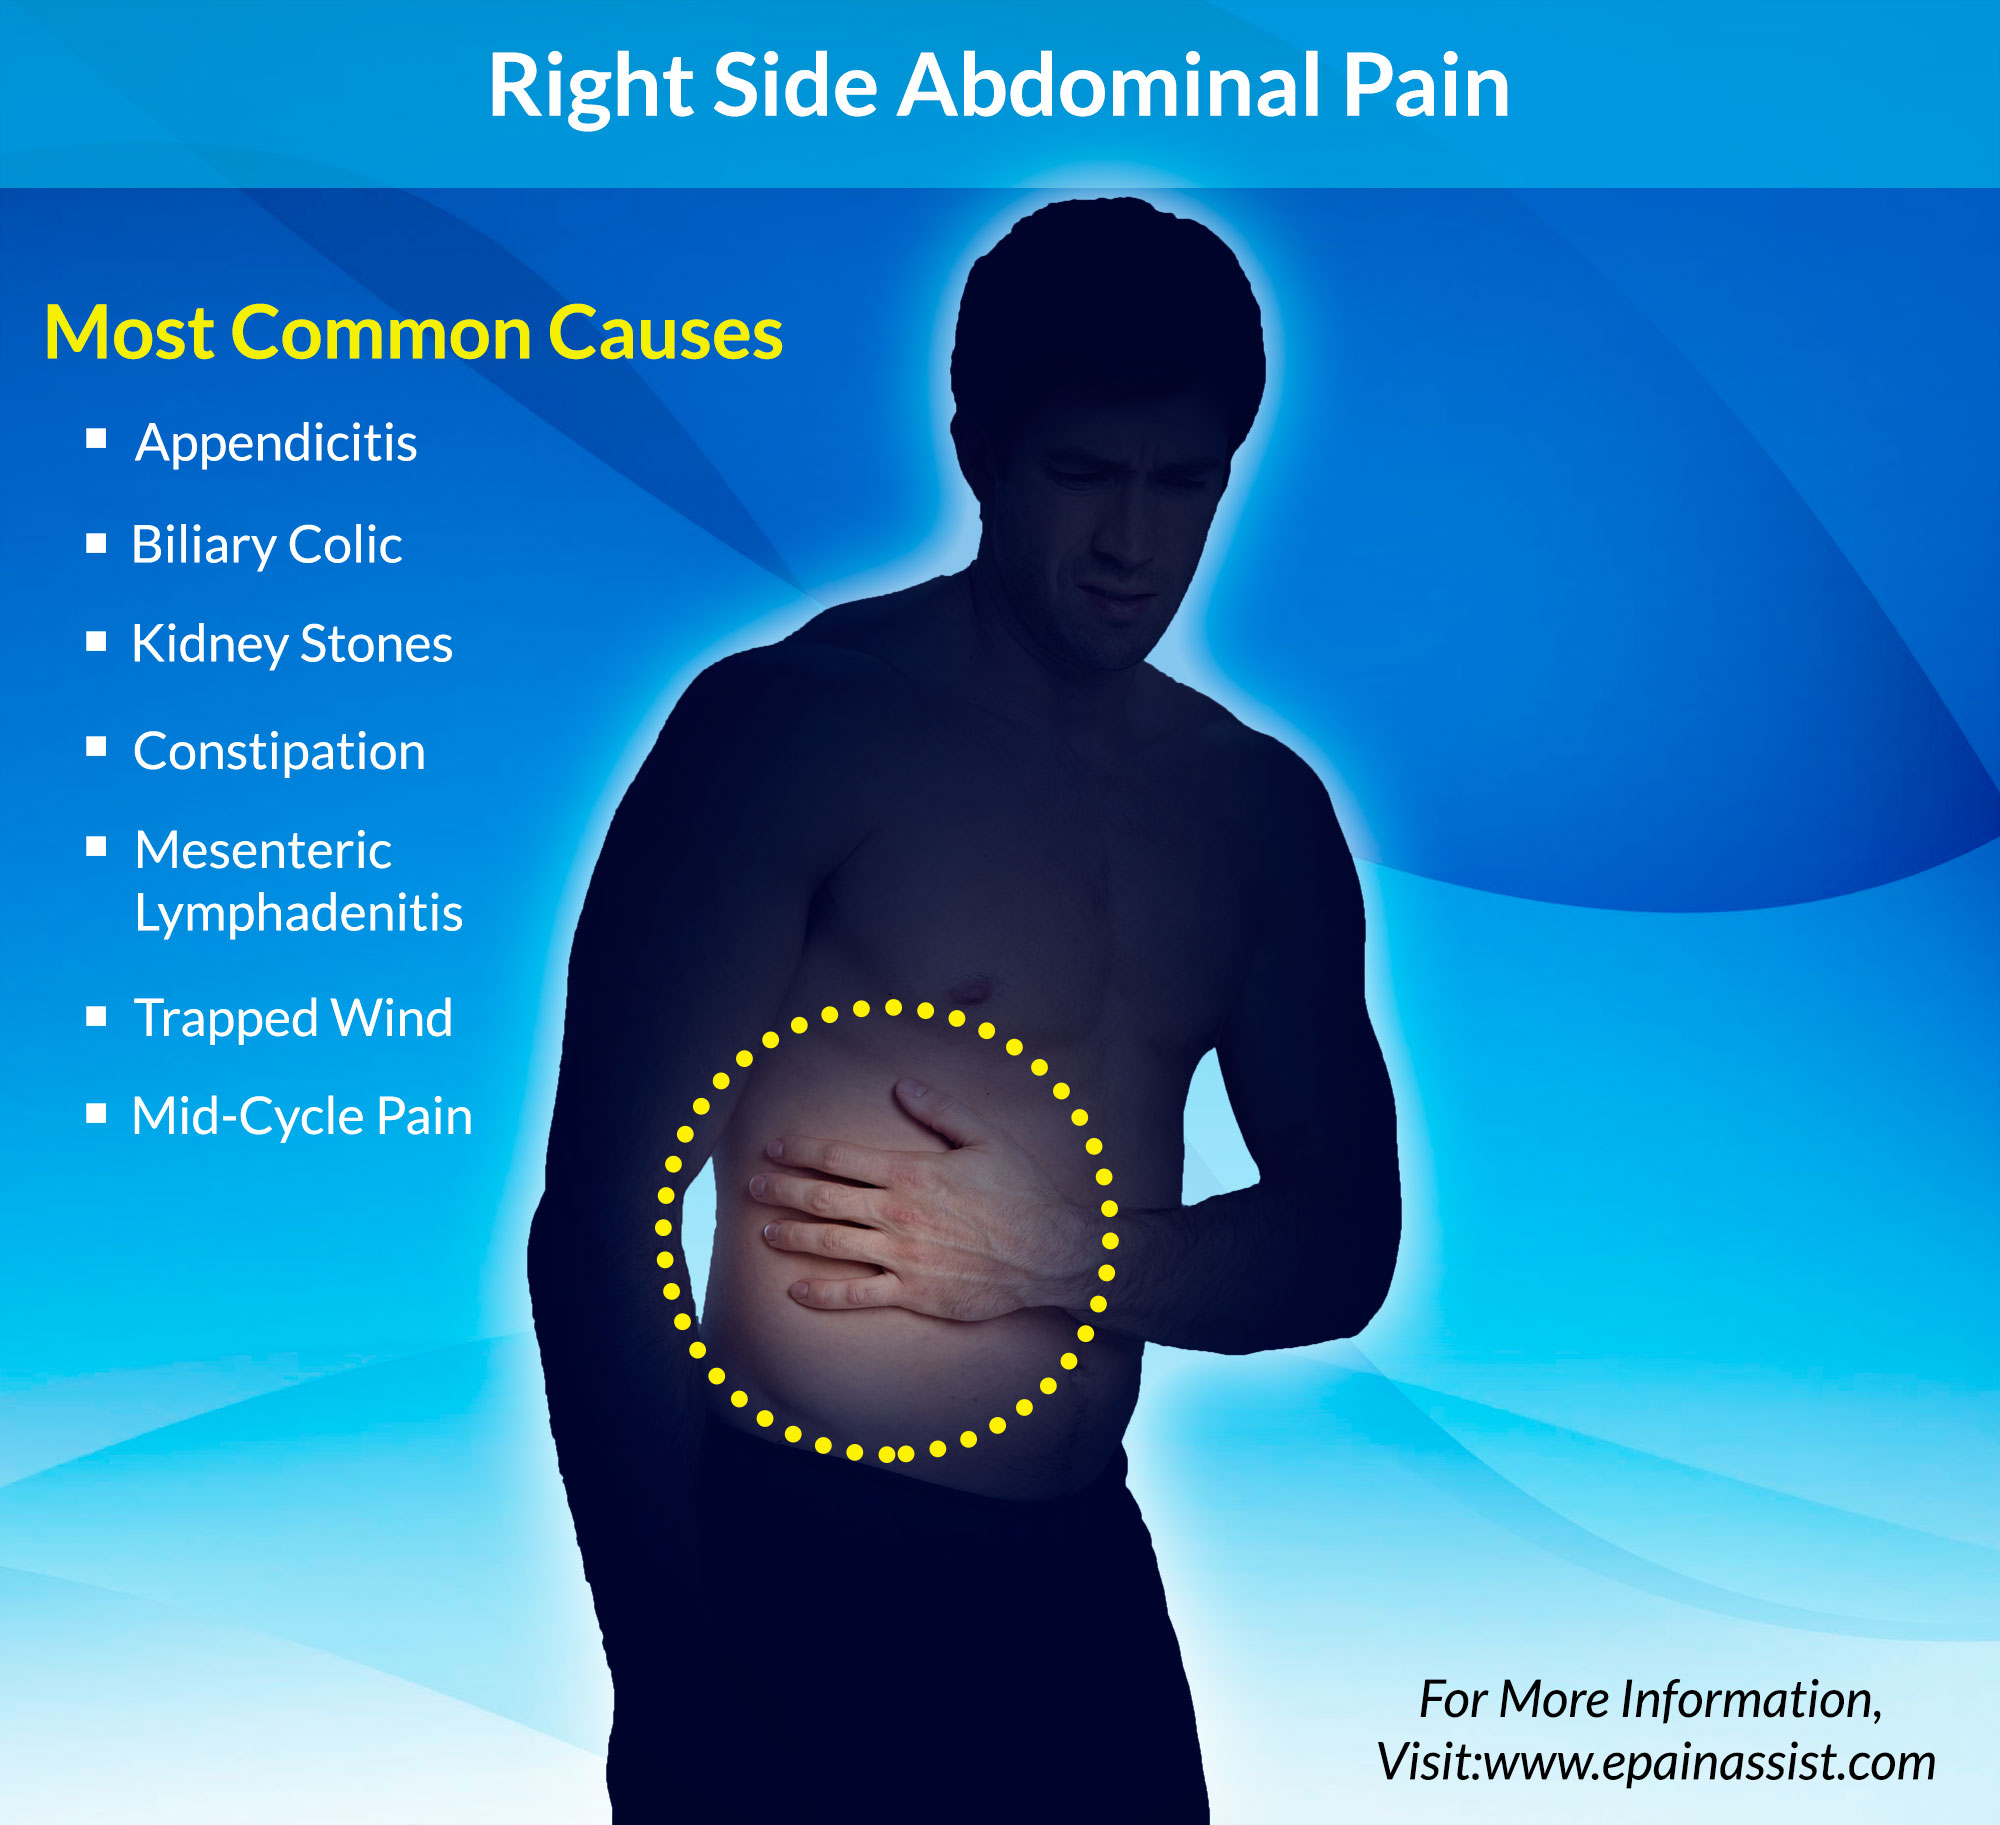

Causes of Pain in the Right Side | New Health Advisor

What Can Cause Right Side Abdominal Pain?

Lower Abdominal Pain: Symptoms And Causes – Forbes Health

Abdominal pain | Health | Pinterest | Pain d’epices and Abdominal pain

Female Abdominal Pain | Types | Symptoms | Causes | Diagnosis | Treatment

What Is Pain In Lower Right Side Of Stomach – StomachGuide.net